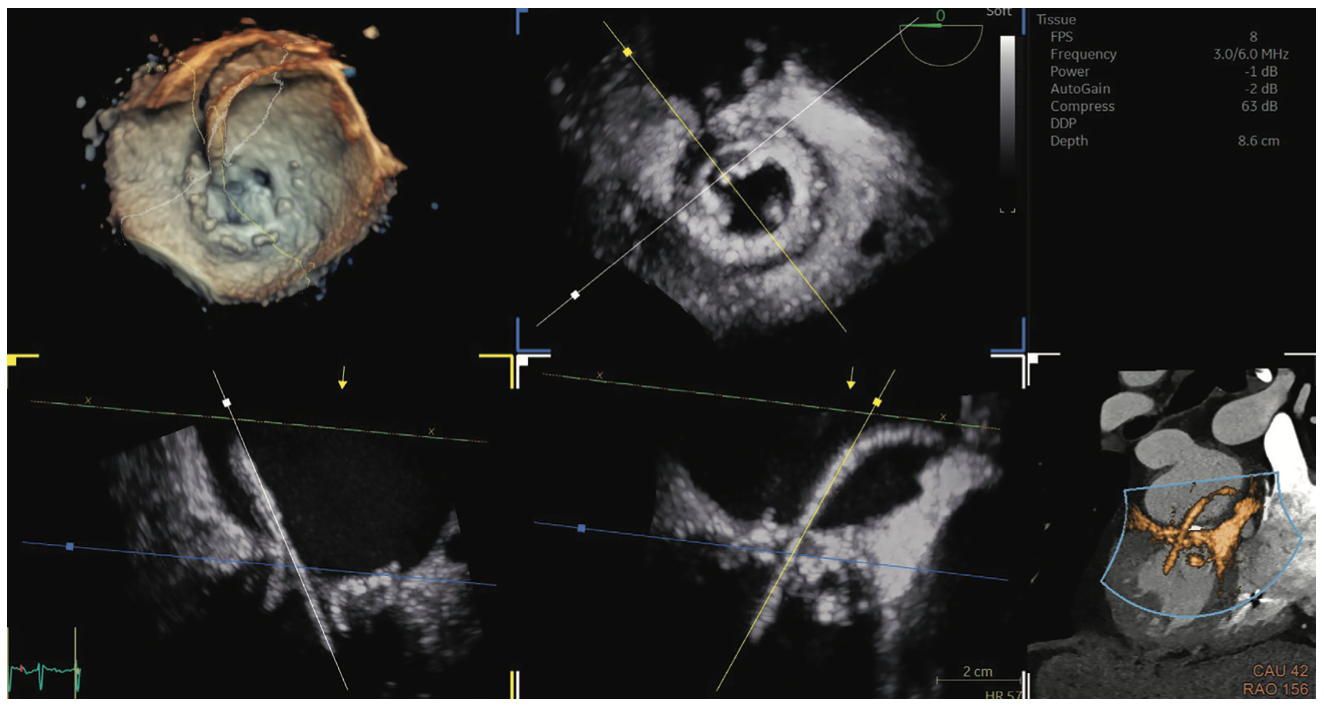

Praveen Mehrotra, MD: There are several echocardiographic technologies, recently developed, that help to solve some of the imaging challenges during structural heart procedures. First and foremost is the need for outstanding 3D volumetric and multiplanar imaging with high spatial resolution and frame rates. We use live 3D imaging to help guide certain procedures and to obtain critical measurements prior to the start of the procedure, usually for device sizing. There is a new technology called 4D Markers (GE HealthCare), which we can place on 2D and 3D echo images. The interventional cardiologist can view the 4D Markers onscreen and use them as a target, so he or she knows where we are asking them to direct a wire or catheter without the echocardiologist having to verbalize it or struggle to communicate that information. The markers exist in 3D space, so we can see them in multiple views simultaneously. Another useful technology called View-X (GE HealthCare) places the fluoroscopic image adjacent to the TEE image on the echo machine. This technology allows me to visualize the procedure from the standpoint of the interventionalist, integrate fluoroscopic and echocardiographic data, and anticipate what information will be needed next by the interventional cardiologist or surgeon.

In real life, catheters and cardiac structures don’t exist in perfect 2D planes, but in 3D space, so we frequently rely on 3D technology to guide structural heart procedures. We recently performed a transcatheter mitral valve intervention with MitraClip, and we were not able to guide device placement with routine 2D imaging because we couldn’t visualize the MitraClip delivery system in conventional 2D imaging planes. However, we were able to utilize live multiplanar 3D imaging with FlexiSlice (GE HealthCare), which allowed us to manipulate the imaging planes such that the guide catheter, delivery system and MitraClip could be visualized in a single imaging plane. The technology allowed us to visualize and implant the device with ease, resulting in a good outcome for the patient.

We are also starting to use fusion technology. There are several different types of fusion imaging technology currently available on the market; one recently released fusion technology is CT-Echo Fusion (GE HealthCare) that fuses previously acquired CT data to the live 3D echo image. Echocardiography can suffer due to dropout from calcification or devices. This fusion technology allows us to integrate CT imaging that we already utilize for pre-procedural planning of structural heart procedures and integrate that with the echocardiographic images obtained on the day of the procedure. These fusion technologies are currently evolving and may prove to be very useful in complex structural heart procedures where echocardiography alone may not be sufficient.

Another new technology called FlexiLight imaging (GE HealthCare) is a new 3D rendering technique that provides photorealistic, light-source-based illumination of heart structures that help the imager with depth perception when visualizing cardiac structures. This imaging technique can provide realistic detail of the contours of cardiac structures that we have not been able to appreciate previously. FlexiLight can also potentially better illustrate the interaction of devices with valve leaflets, or when complications such as leaflet perforation may have occurred.